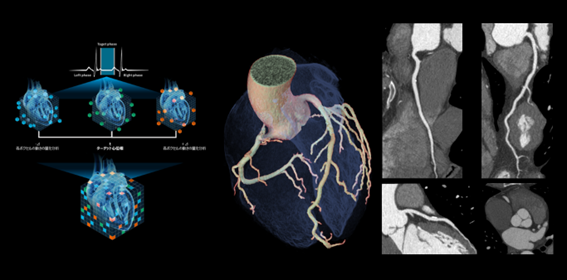

160mmワイドカバレッジCTの有用性が最も活かされる領域の一つとして、循環器領域・心臓CTが挙げられます。近年では、循環器臨床における治療、特に経カテーテル的治療の進歩により、冠動脈の評価だけでなく、弁や心房等、冠動脈以外の術前心臓CT評価のニーズも増えており、従来以上に心臓全体でのモーションアーチファクトの低減が重要となっています。このことからGEヘルスケアでは独自の動態ベクトル解析を用いたモーション抑制アルゴリズムSnapShot Freeze2.0(SSF2.0)により、心臓全体のモーションアーチファクトの抑制に取り組んできました。TAVI、経皮的僧帽弁クリップ術、更には三尖弁においても径カテーテル的治療の広がりが期待されていますが、三尖弁は薄く、また距離・位置的にも経食道心エコーでの評価が難しいケースがあります。Revolution Apex Eliteでは最速0.23秒回転を実現し、SSF2.0と組み合わせることで他モダリティでも評価が難しい領域の画像化も期待でき、これら技術が開胸を行わない非侵襲的治療の安全実施に貢献します。

※(左 ) SnapShot Freeze2.0の概念図

ターゲット心位相とその前後の心位相の合計3心位相のフェーズデータを用いて、心臓を構成する各ボクセルの 動態を3次元的にベクトル解析し、変化量をフィードバックし静止画像を生成

※(右 ) 70kV, 0.23秒/回転で撮影した心臓CT画像